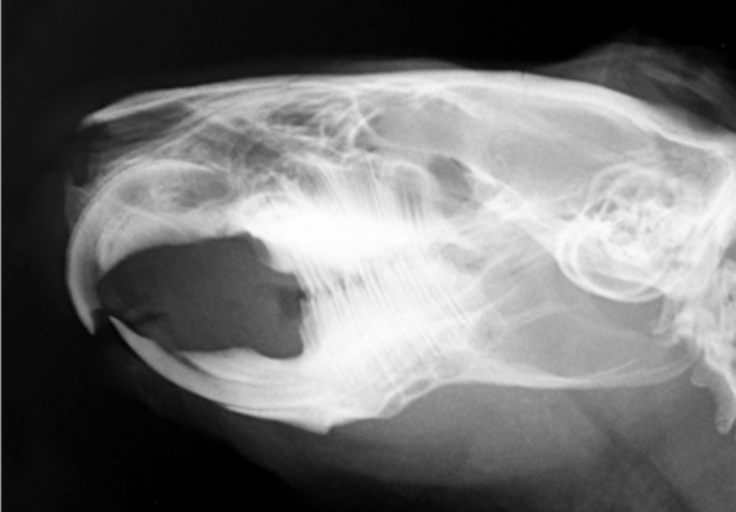

Q

A

rabbit